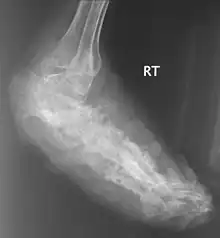

![]() | |

| An infected foot | |

X rays and ultrasonography may be carried out to assess the extent of the disease. X rays findings are extremely variable. The disease is most often observed at an advanced stage that exhibits extensive destruction of all bones of the foot. Rarely, a single lesion may be seen in the tibia where the picture is identical with chronic osteomyelitis. Cytology of fine needle aspirate or pus from the lesion, and tissue biopsy may be undertaken sometimes.[11] Some publications have claimed a "dot in a circle sign" as a characteristic MRI feature for this condition (this feature has also been described on ultrasound).[14]